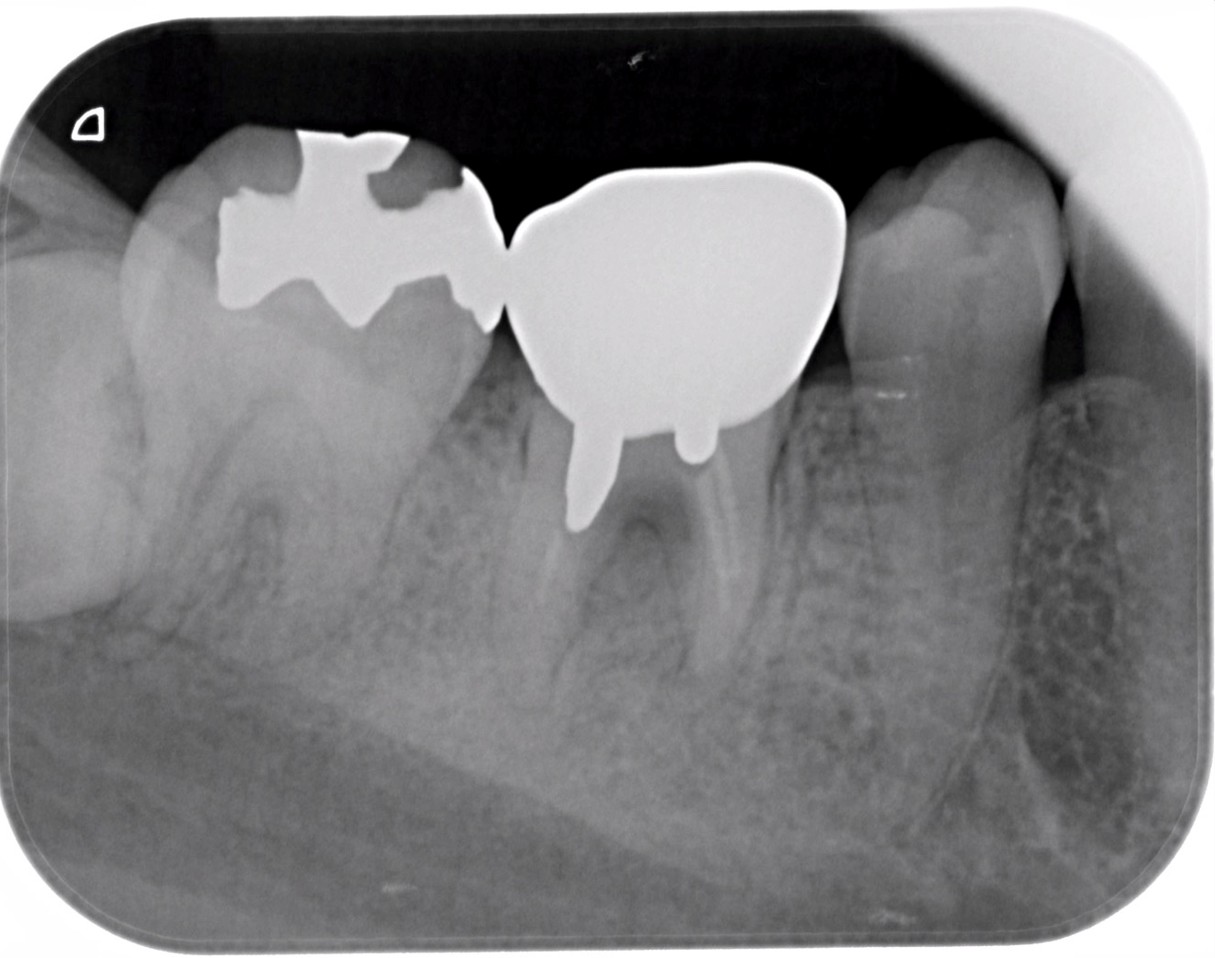

症例1:パーフォレーションリペア症例

(歯の中に大きな穴が空いてしまっているのを埋めて再生を促す治療)

歯に穴が空いていて骨に炎症がある状態 |

CTでも歯の周囲に骨がないのが分かる。 |

BEFORE |

AFTER |

人為的根穿孔を起こした部分に感染を起こしており、歯周ポケットが9㎜ありました。 ラバーダム防湿とマイクロスコープを使用して丁寧に治療を行いました。 殺菌性があり歯を補強することのできるMTAという根管充填材料を使用して、歯周ポケットは2㎜に改善しました。 |